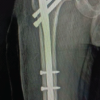

In our study, the mean age of the patients with IT fracture is 71.29 years with majority being in 71–80 years of age group (38.67%), followed by 32% in 61–70 years of age group. Among the 75 patients with IT fracture, 41 patients are males and 34 are females, amounting to 54.67% of males and 45.33% of females. In our study among 75 patients of IT fractures, 38 patients had right-side injury and 37 patients had left-side injury. Right side is common side in our study. In our study, we classified IT fractures according to Evan’s classification. Among 75 patients, 17 patients had Evan’s Type 1, Group 1 IT fracture; 21 patients had Evan’s Type 1, Group 2 IT fracture; 12 patients had Evan’s Type 1, Group 3 IT fracture; 18 patients had Evan’s Type 1, and Group 4 IT fracture and 7 patients had Evan’s type 2 IT fracture. In our study, mean operating time of PFN group is 92.80 min, MS-PFN group is 78 min and A2-PFN group is 66.8 min. Significant difference seen in PFN versus MS-PFN and PFN versus PFN-A2. There is no significant difference between MS-PFN and PFN-A2 group. In our study, mean blood loss in PFN group is 307.2 mL; in PFN-A2 group, it is 237.2 mL and in MS-PFN group, it is 246.4 mL. Significant difference is seen in PFN versus MS-PFN and PFN versus PFN-A2. There is no significant difference between MS-PFN and PFN-A2 group. In our study, mean radiological union in PFN group is 15.89 weeks; in MS-PFN group, it is 14.92 weeks; and in PFN-A2 group, it is 13.14 weeks. There is significant difference between PFN and PFN-A2 group in terms of union. In our study, we compared Harris hip score among three groups at post-operative 6 weeks, 12 weeks, 6 months, and 1 year. The results are tabulated in Tables 2 and 3, Graph 1. There is significant difference between PFN and PFN-A2 group in terms of functional outcome. In our study, we compared anterior thigh pain among three groups. Anterior thigh pain is more in PFN with 52%, followed by PFN-A2 with 40% and less in MS-PFN group with 27% (Table 4). PFN group had 12% shortening, 8% of screw cut out, 8% of SSI, 4% of varus collapse, and 4% of Z effect/reverse Z effect. PFN-A2 group had 4% shortening, no screw cut out, 8% of SSI, and 4% of varus collapse. MS-PFN group had 8% shortening, 4% of screw cut out, no SSI, no varus collapse, and 4% of Z effect/reverse Z effect (Table 5).

The average intraoperative blood loss in PFN group was 307.20 mL. PFN-A2 group had an average blood loss of 237.20 mL and MS-PFN had an average blood loss of 246.40 mL. Average blood loss was least in PFN-A2. In a study on PFN by Chopra et al. [10], average blood loss during surgery is 126 mL. In a study on MS-PFN by Jha and Ahmed [6], average blood loss is 130 mL and in a study on PFN-A2 by Rai et al. [11], average blood loss is 200 mL. In our study average radiological union in PFN group is 15.89 weeks; in MS-PFN group, it is 14.92 weeks and in PFN-A2 group, it is 13.14 weeks. Union in PFN-A2 is earlier compared to PFN and MS-PFN. In a study on PFN by Gadegone and Salphale [12], average time for fracture consolidation is 18 weeks. In a study on MS-PFN by Jha and Ahmed [6], average time for radiological union is 17.32 weeks and in a study on PFN-A2 by Rai et al. [11], it is 13.8 weeks. In our study, average mean Harris hip score for PFN-A2 is higher compared to PFN and MS-PFN at post-operative 6 weeks, 12 weeks, 6 months, and at 1 year. Harris hip score for PFN at 1 year is 82.26, for MS-PFN, it is 86.18, and for PFN-A2, it is 88.81. At post-operative 1 year, Harris hip score is higher in PFN-A2 group, followed by MS-PFN group compared to PFN group. All three implants have given good functional outcome according to Harris hip score. In a study on PFN by Mandice et al. [13], Harris hip score at 6-month post- operative is 88.75 and in a study on PFN-A2 by Rai et al. [11], it is 85.08 at 6-month post-operative. In our study, among 25 patients of PFN, 13 patients had persistent anterior thigh pain, among 25 patients of PFN-A2 of 240 mm, 15 patients had anterior thigh pain. However, in our MS-PFN group, it was significantly low, only 4 patients complained of anterior thigh pain out of 25 patients. In a study on PFN by Mukherjee et al. [14], 16 out of 53 patients had anterior thigh pain. In a study on PFN-A2 by Kumar et al. [15], 3 among 25 patients experienced anterior thigh pain. In our study, among 75 patients, 3 in PFN group, 2 in MS-PFN group, and 1 in PFN-A2 group had >1 cm of shortening. In a study on PFN by Chopra et al. [10], out of 125 patients, 3 had shortening. In a study on MS-PFN by Jha and Ahmed [6] out of 120 patients, 9 patients had shortening. Moreover, in a study on PFN-A2 by Rai et al. [11], among 25 patients, 2 patients had shortening. 2 patients in PFN group and 1 in MS-PFN group had complication of screw cutout; 2 in PFN group and 2 in PFN-A2 group had surgical site infection; 1 in PFN group and 1 in PFN-A2 group had varus collapse; and 1 in PFN group and 2 in MS-PFN group has Z effect/reverse Z effect. In a study on PFN by Chopra et al. [10], out of 125 patients, 5 had Z effect/reverse Z effect. In a study on MS-PFN by Jha and Ahmed [6] out of 120 patients, 14 patients had above-mentioned complications and in a study on PFN-A2 by Rai et al. [11], among 25 patients, 2 patients had varus collapse and 1 patient had surgical site infection.

PFN-A2 is superior in terms of operating time, intraoperative blood loss, functional outcome, and fracture union. MS-PFN is next to PFN-A2 in the above parameters followed by standard PFN. Anterior thigh pain was significant among patients with nails of 240 mm length (standard PFN and PFN-A2), compared to 180mm length nail (MS-PFN). Hence, to avoid anterior thigh pain, we recommend the use of shorter nails (180 mm length).

For the intertrochanteric fractures of femur not extending beyond lesser trochanter, we recommend the use of PFN A2 of 180mm length.